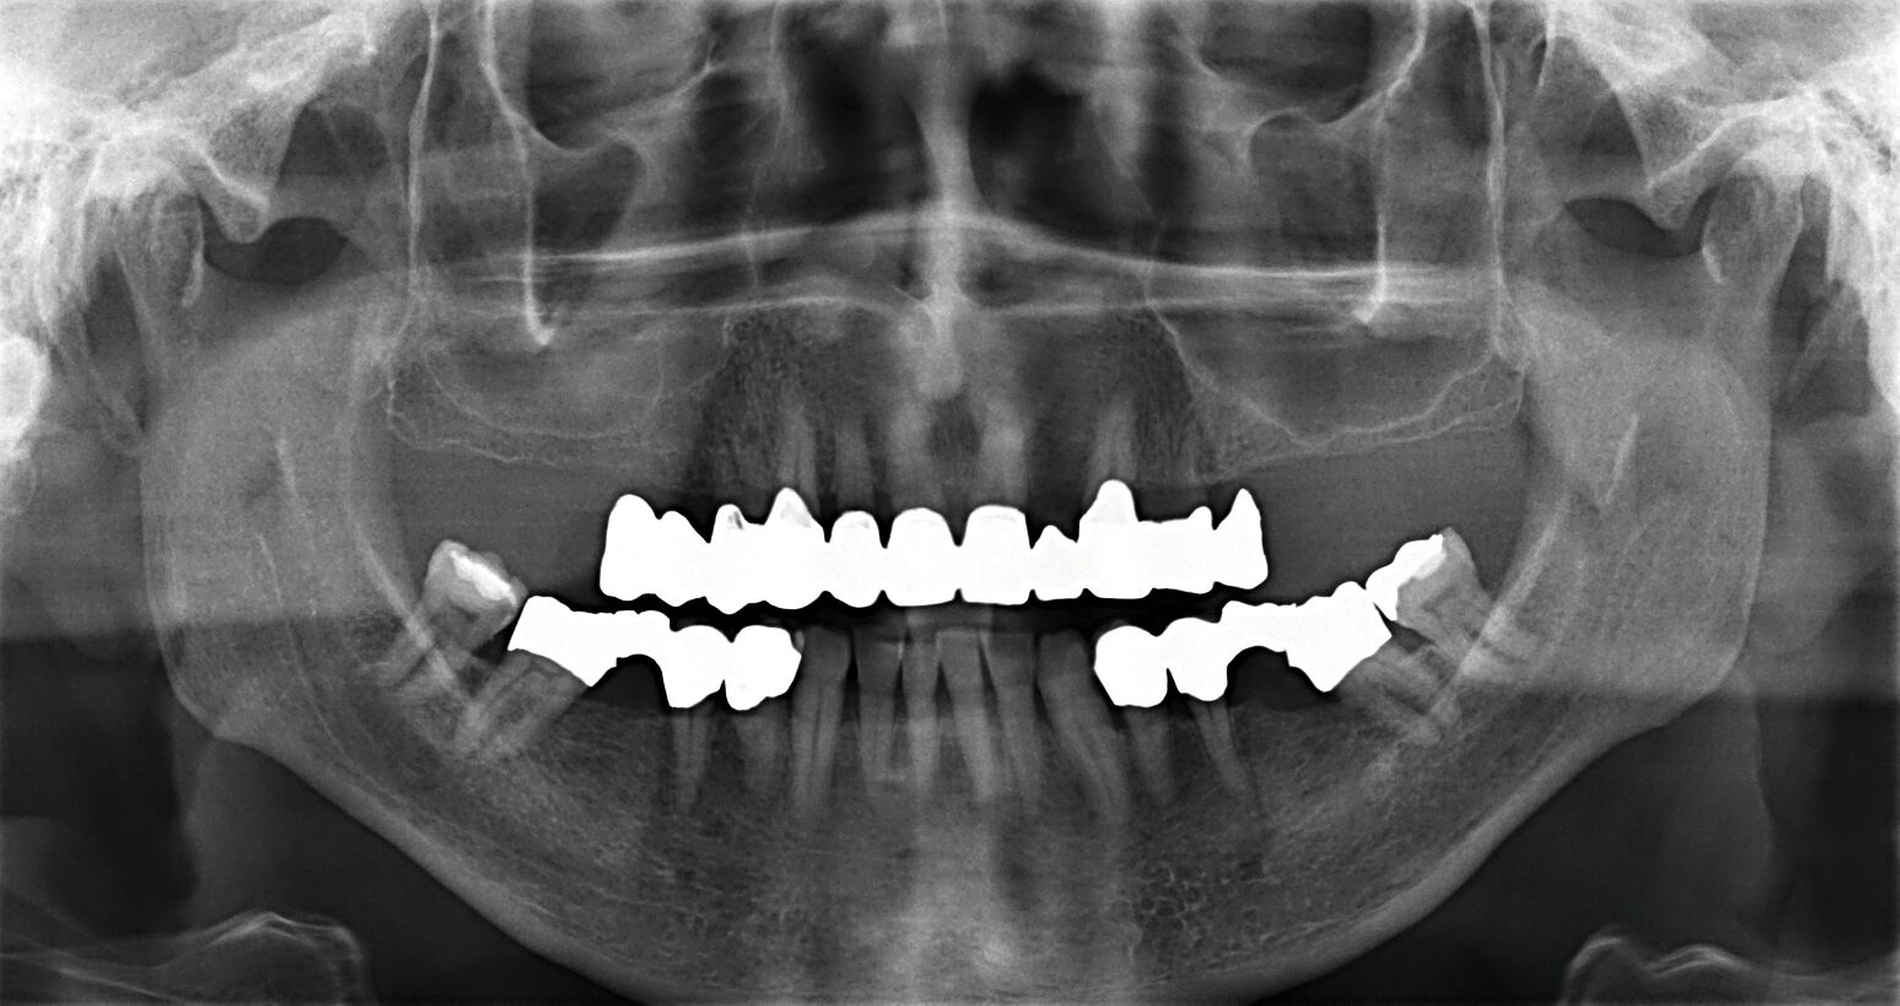

Nach Durchführung einer dentalen Volumentomografie (DVT) wurden daher zahnärztliche Implantate in Regio 14, 15 und 25 im Sinne einer verkürzten Zahnreihe geplant und inseriert (Abbildung 7). Nach dreimonatiger subgingivaler, konventioneller Einheilzeit wurden die Implantate freigelegt. Zwei Wochen später begann man die vorhandenen Primärkronen zu entfernen. Die Stümpfe wurden nachpräpariert und es wurden erneut Fäden gelegt (Abbildung 8a und 8b).

Um den Sitz der Implantatkronen nach dem Einsetzen zu prüfen, wurden intraorale Tubusaufnahmen im Sinne eines Baseline-Röntgens angefertigt (Abbildung 9). In den Folgeterminen wurde dem Patienten noch eine Aufbissschiene für den Oberkiefer eingegliedert, um etwaigem nächtlichen Bruxismus vorzubeugen. Für die Nachsorge empfiehlt sich ein halbjährliches Kontrollintervall.